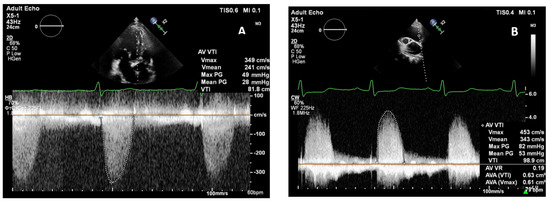

| Vmax AV, cm/s | A5C | 467 [428; 520] | 346 [310; 367] | <0.001 * |

| RPW | 471 [431; 521] | 439 [412; 487] | 0.119 | |

| p | 0.429 | 0.429 | <0.001 * ↑ (100.0%), ↓ (0.0%) | |

| ΔPmean, mm Hg | A5C | 53 [44; 70] | 29 [25; 33] | <0.001 * |

| RPW | 52 [39; 63] | 43 [38; 56] | 0.175 | |

| p | 0.183 | 0.183 | <0.001 * ↑ (95.5%), ↓ (4.5%) | |

| VTI AV, cm | A5C | 118 [103; 136] | 80 [72; 82] | <0.001 * |

| RPW | 114 [101; 130] | 106 [97; 109] | 0.029 * | |

| p | 0.325 | 0.325 | <0.001 * ↑ (90.9%), ↓ (9.1%) | |

| AVA (VTI), cm2 | A5C | 0.61 [0.52; 0.81] | 1.19 [1.02; 1.27] | <0.001 * |

| RPW | 0.63 [0.52; 0.82] | 0.84 [0.62; 0.92] | 0.099 | |

| p | 0.244 | 0.244 | <0.001 * ↑ (9.1%), ↓ (90.9%) | |

| AVAi, cm2/m2 | A5C | 0.33 [0.27; 0.40] | 0.60 [0.58; 0.65] | <0.001 * |

| RPW | 0.35 [0.28; 0.42] | 0.42 [0.29; 0.46] | 0.131 | |

| p | 0.251 | 0.251 | <0.001 * ↑ (9.1%), ↓ (90.9%) | |